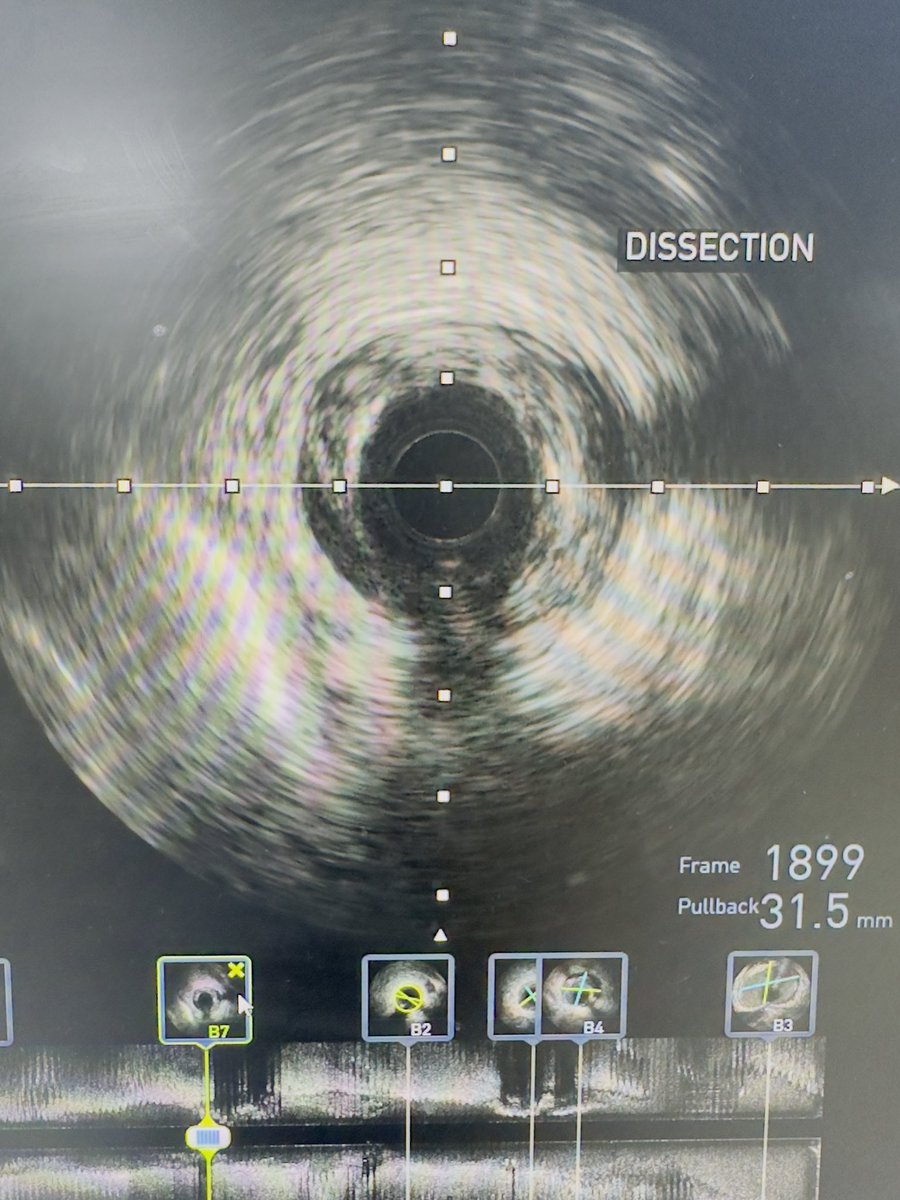

IVUS helps us eliminating guesswork in decision making process. Diffuse LAD lesion. After pre-dilatation, angiography show no flow distally. Conducted an IVUS ➡️ dissection revealed ➡️ we treated with stenting. Flow restored, good final result 😇 #interventionalcardiology

IVUS helps us eliminating guesswork in decision making process.

Diffuse LAD lesion. After pre-dilatation, angiography show no flow distally.

Conducted an IVUS ➡️ dissection revealed  ➡️ we treated with stenting.

Flow restored, good final result 😇